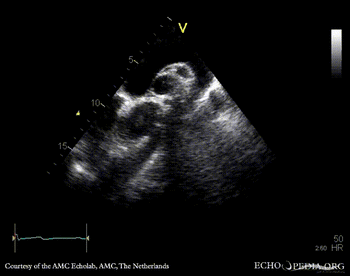

| Courtesy of: AMC Echolab, AMC, The Netherlands | |

| Suprasternal view | |